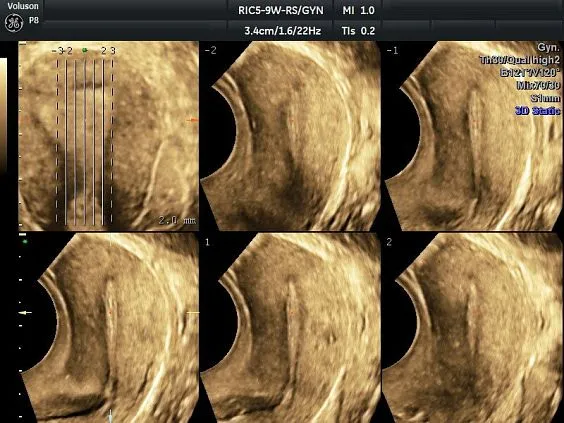

Клинические изображения

Несмотря на демократичную цену, Voluson P8 обеспечивает изображение экспертного уровня, включая поддержку 3D/4D-визуализации, что делает его востребованным в акушерстве и гинекологии. Он построен на платформе Voluson Core Architecture, которая гарантирует высокое качество двухмерной и трёхмерной визуализации, а также стабильную производительность при рутинных исследованиях.

Voluson P8 одинаково уверенно справляется как с задачами в сфере женского здоровья (оценка развития плода, диагностика патологий малого таза), так и при сканировании сердца, сосудов, органов брюшной полости и поверхностных структур. Аппарат поддерживает современные технологии обработки изображения: HD-Flow™, Speckle Reduction Imaging (SRI), CrossXBeam™, что позволяет получить максимально чёткие и информативные данные даже в сложных клинических условиях.

- Томографический ультразвук (TUI)

Простота получения 3D-изображений

Визуализация в режимах 3D/4D позволяет исследовать дополнительные анатомические плоскости, повышая вашу уверенность в диагностике.

- Визуализация плоскостей недоступных для исследования при 2D-сканировании, для более точной диагностики.

- Высокая производительность, благодаря возможности анализировать 3D данные как во время, так и после завершения исследования.

- Просмотр и обработка объемных изображений в разных плоскостях или с использованием разных режимов сканирования.